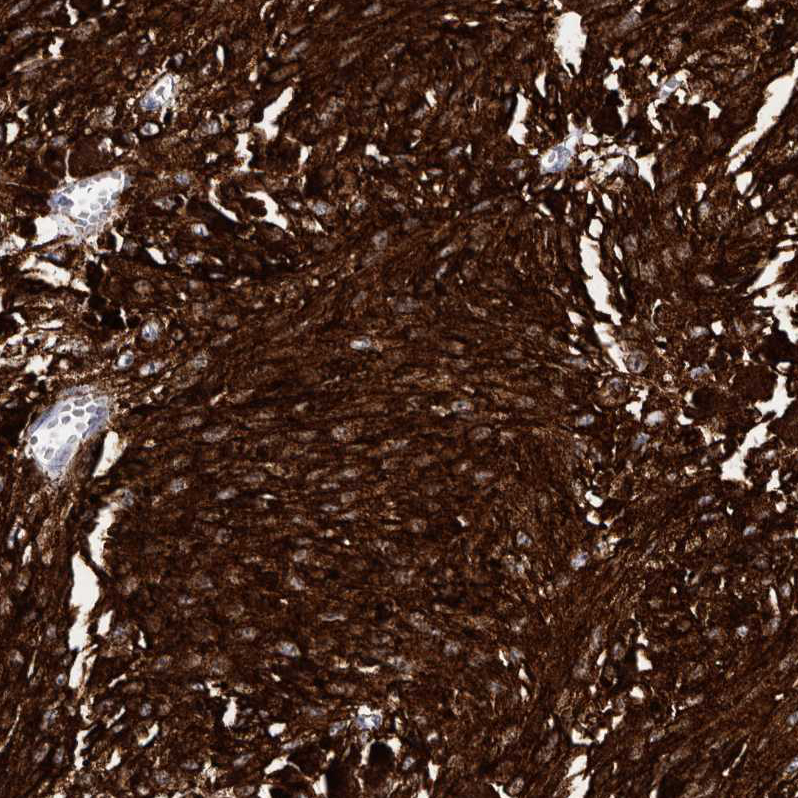

Immunohistochemical staining of human malignant melanoma shows strong cytoplasmic positivity in tumor cells.